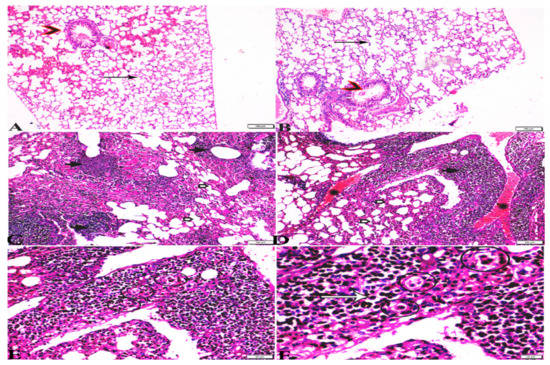

3.3. Histopathological Findings